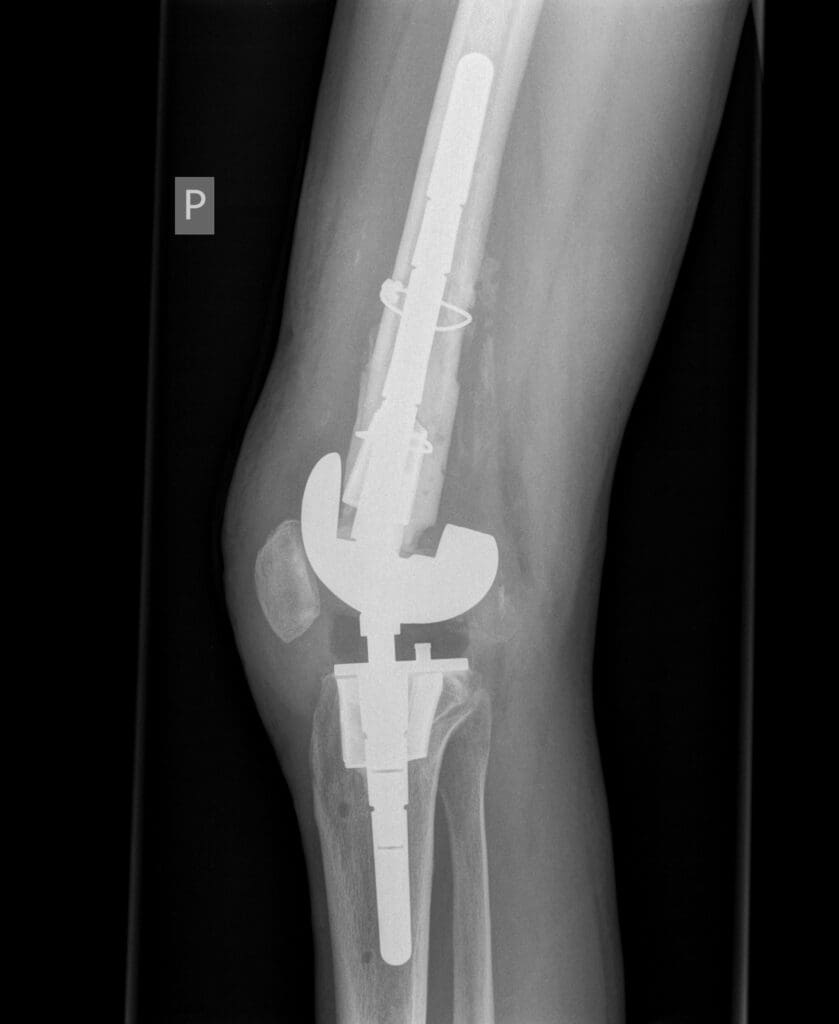

Po ustabilizowaniu najgroźniejszych obrażeń konieczne było przeprowadzenie kilku poważnych operacji ortopedycznych. Jednym z najtrudniejszych wyzwań było zrekonstruowanie kolana, które w wyniku wypadku uległo niemal całkowitemu zniszczeniu. Fragmenty kości uległy martwicy i rozpadowi, co znacząco utrudniało możliwości dalszego leczenia.

Lekarze z Kliniki Urazowo-Ortopedycznej pod kierownictwem dr. Rafała Wójcickiego przeprowadzili innowacyjny zabieg rekonstrukcji stawu kolanowego, stosując nowoczesne materiały i cement kostny. Było to kluczowe dla dalszej terapii, ponieważ umożliwiło odbudowę ubytków kostnych i przygotowanie pacjenta do kolejnych etapów leczenia.

Po kilku miesiącach rehabilitacji przystąpiono do kolejnego zabiegu – usunięcia czasowej protezy i wszczepienia endoprotezy stawu kolanowego. Dzięki nowoczesnym implantom udało się przywrócić funkcjonalność kończyny.